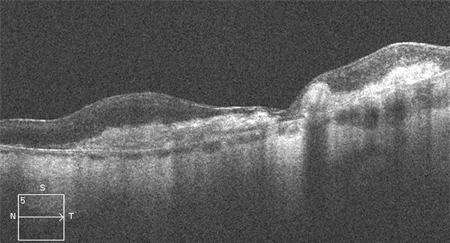

OCT can be used to test for or confirm the presence of subretinal or intraretinal fluid, the degree of retinal thickening (which may not be apparent on biomicroscopy alone), and, with OCT angiography, confirm the presence of macular neovascularisation (MNV), fibrosis and a hyper-reflective (fibrovascular) scar.[4][41][Figure caption and citation for the preceding image starts]: High resolution optical coherence tomography image showing subretinal and intraretinal fluidReproduced from Scheie Eye Institute's patient image database; used with permission [Citation ends].